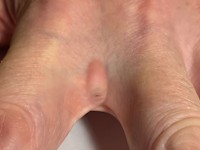

Barber's pilonidal sinus